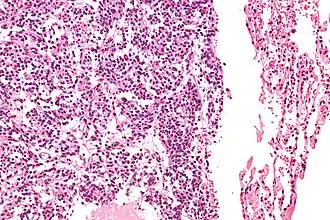

| Micrografia de um típico tumor carcinoide pulmonar. | |

O diagnóstico definitivo é alcançado por um exame microscópico, após excisão. Os tumores carcinoides típicos apresentam células com cromatina pontilhada e uma quantidade moderada de citoplasma. Eles realizam menos mitoses e têm uma baixa necrose. Por definição, eles sã0 maiores do que 4 mm em sua maior dimensão.